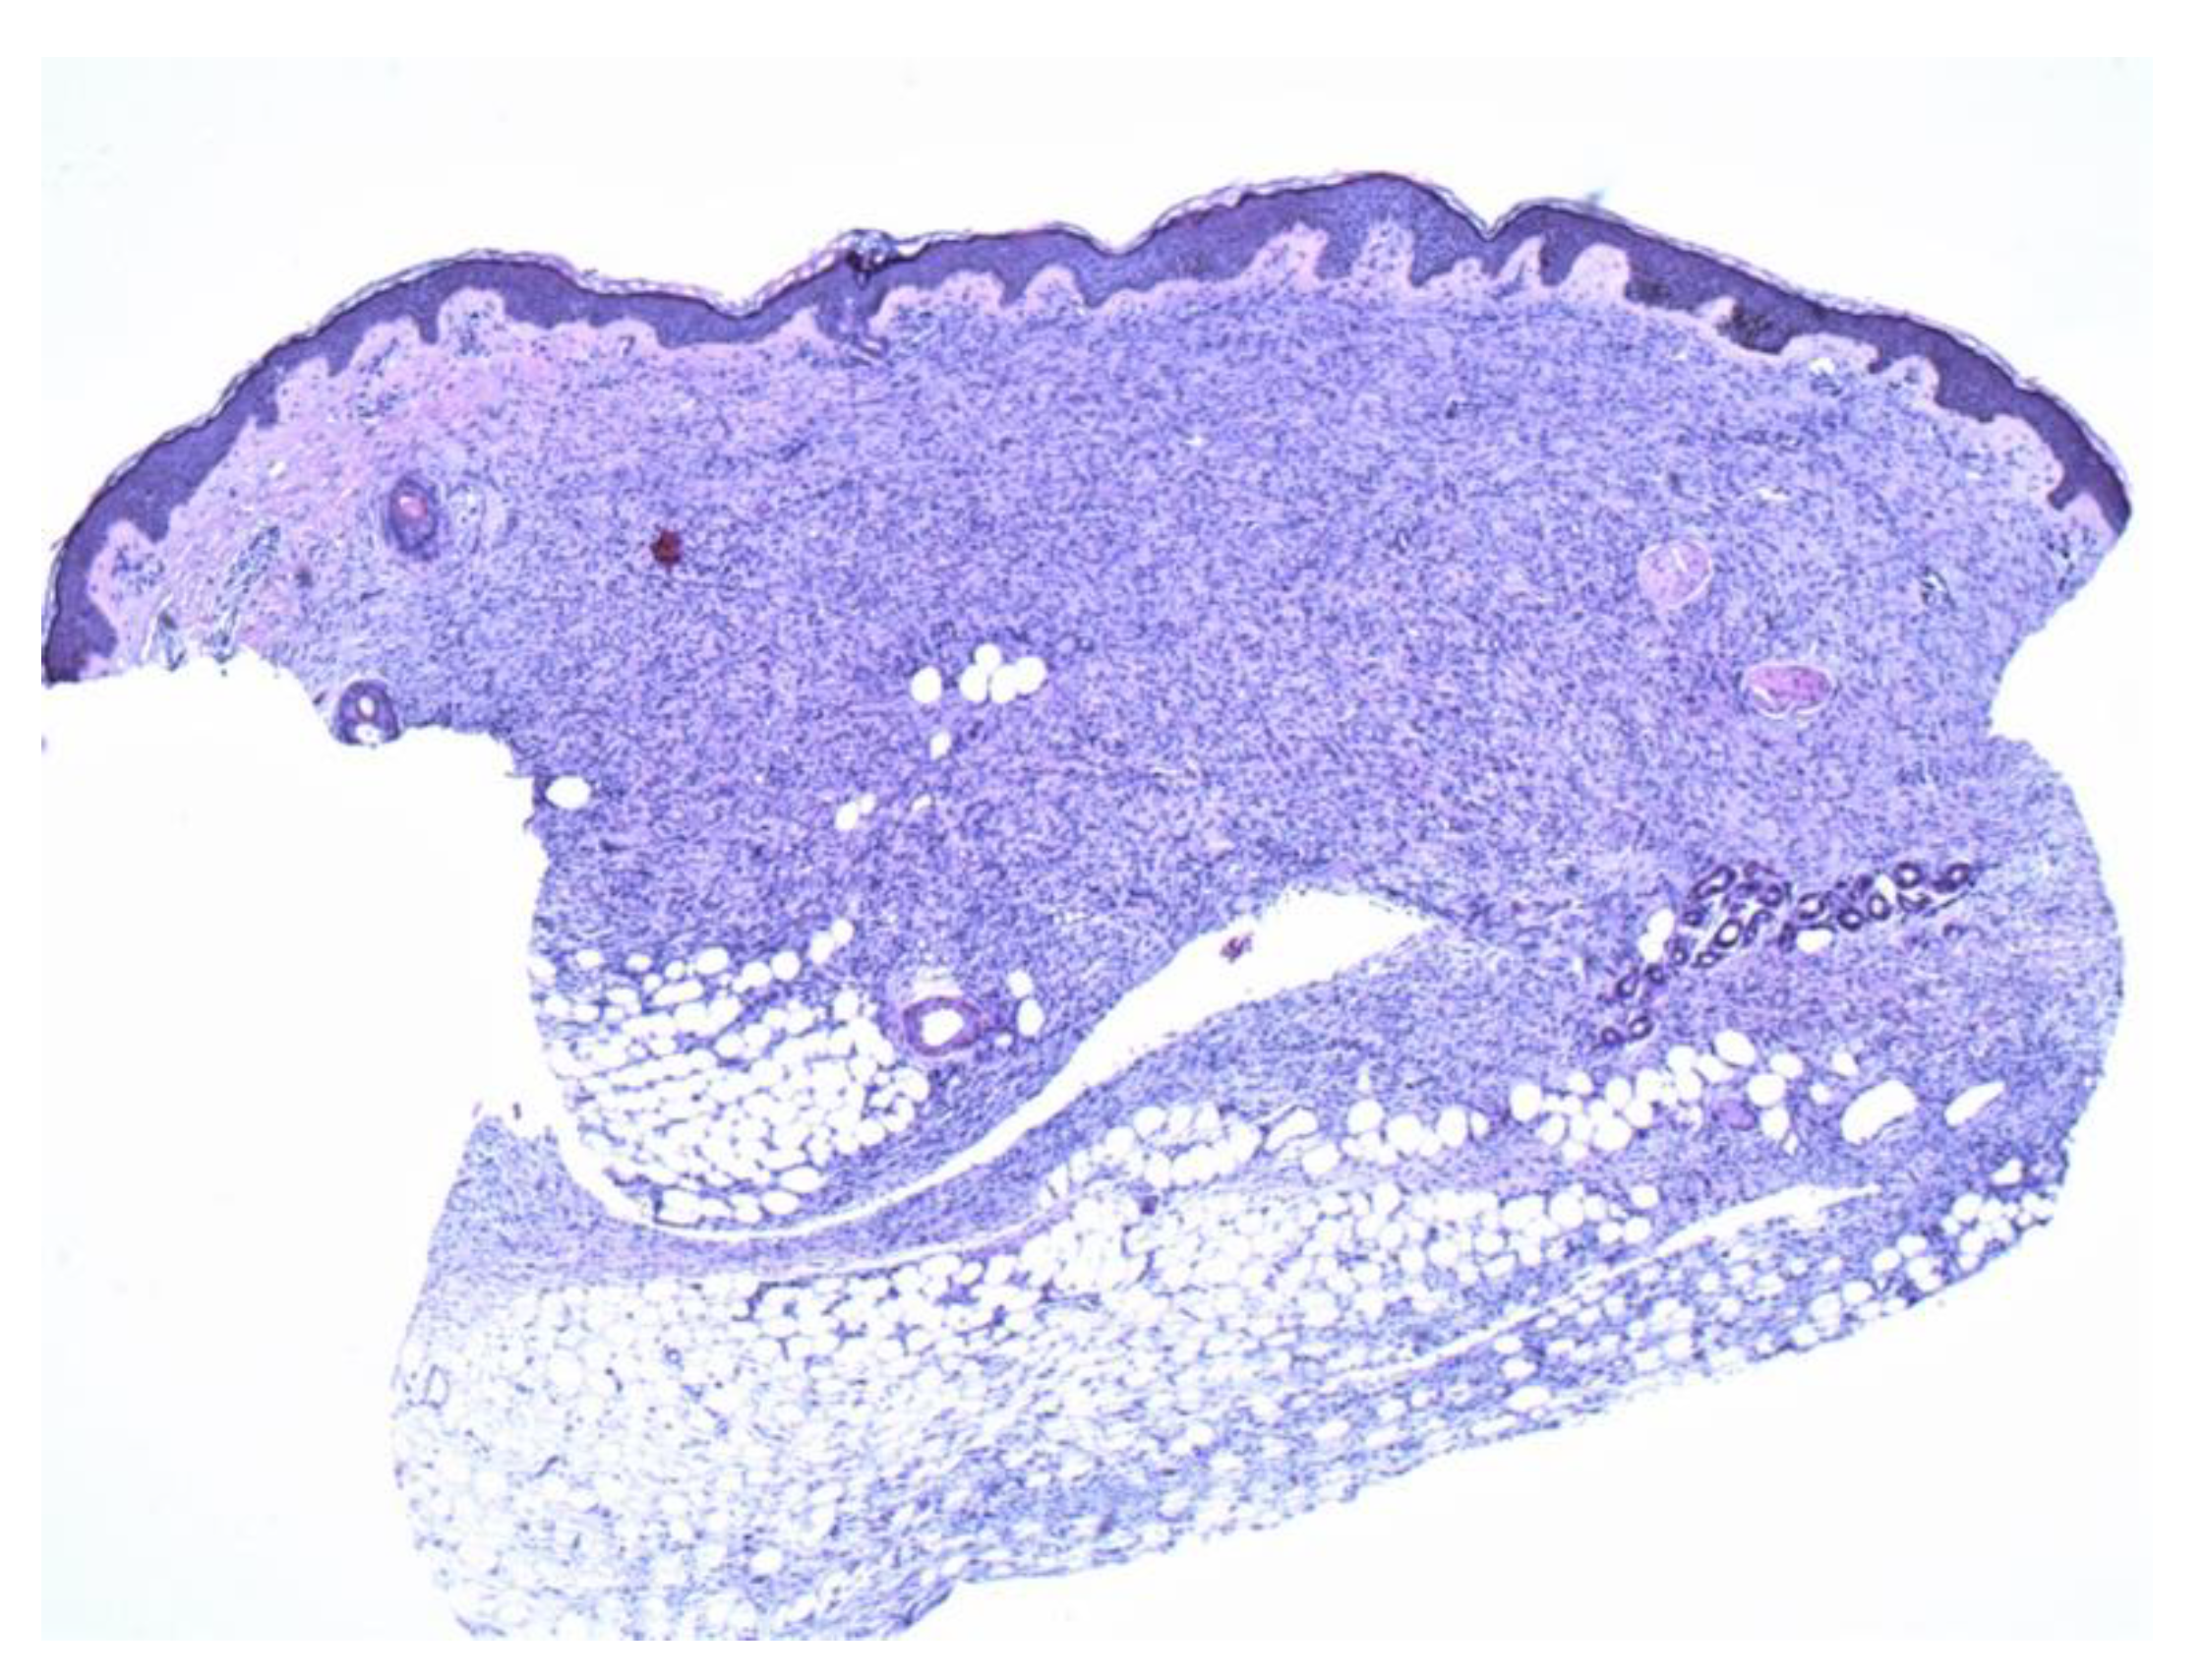

Figure 2.

A thin strip of spindle cells is noted in the deeper dermis with subjacent fat. The mid and superficial dermis show sparse spindle cells with atrophic changes (4×).